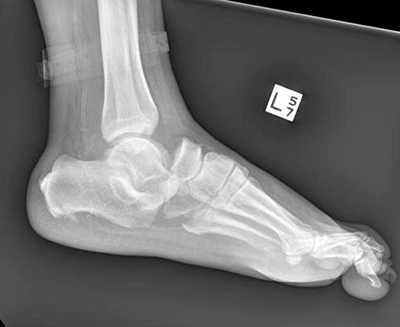

Пациент М. 1980 г.р., травму получил при падении на стопы с высоты 1,5 метра. Лечился по месту жительства (в травмпункте районной больницы) консервативно в гипсовой повязке в течение 14 дней. Консультирован в травматологическом отделении ФГБУ «УНИИТО им. В.Д. Чаклина» Минздрава РФ, предложено оперативное лечение. При поступлении кожные покровы стопы чистые, без признаков воспаления и сдавления тканей. Стопа отечна, уплощена. На рис. 1 представлены рентгенограммы пациента. Прооперирован через 2 недели после травмы. Операция состоит из двух этапов. Первый этап заключается в наложении дистракционного аппарата. Проводятся две спицы 1,8 мм во фронтальной плоскости: первая через нижнюю треть диафиза большеберцовой кости, вторая через бугор пяточной кости (рис. 2). Спицы фиксируются в дистракционном аппарате, выполненном из двух полуколец, соединенных между собой двумя телескопическими тягами. Особое расположение полуколец, фиксация спиц на концах полуколец, крепление кронштейнов для телескопических тяг обеспечивает тракцию пяточной кости в необходимом направлении с использованием минимального количества спиц и внешних опор при сохранении необходимого поля обзора для проведения рентгенологического и визуального контроля репозиции и фиксации. Второй этап - закрытая элевация импрессированной суставной поверхности и окончательная репозиция пяточной кости. Через разрез длиной до 1 см по латеральному краю ахиллова сухожилия (рис. 3) в месте его прикрепления к пяточной кости под соответствующий фрагмент подводится элеватор (рис. 4), манипуляцией которым устраняется смещение и выполняется провизорная фиксация спицами 1,5 мм (рис. 5). При сагиттальном раскалывании суставной фасетки целесообразно проведение одного-двух винтов субхондрально (рис. 6). Стержень вводится с дорзальной поверхности пяточной кости по ее оси через разрез до 2 см по предварительно сформированному остеотомом каналу (рис. 7, 8). Далее через проколы кожи с помощью кондуктора (рис. 9) выполняется запирание винтами с латеральной поверхности, внешнее устройство демонтируется. Достигнуто удовлетворительное стояние отломков (рис. 10).

Рис. 1. На рентгенограмме левой стопы в прямой и боковой проекциях определяется оскольчатый внутрисуставной перелом левой пяточной кости

Рис. 10. На рентгенограмме левой стопы в прямой и боковой проекциях определяется удовлетворительное стояние костных фрагментов на фоне металлофиксатора